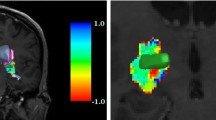

We propose an automatic identification method of sweet spots from MERs for electrodes implantation in STN-DBS. To better imitate the surgeons’ observation and obtain more intuitive contextual information, we first employ the 2D Gramian angular summation field (GASF) images generated from MERs data to perform the sweet spots determination for electrodes implantation. Then, we introduce the convolutional block attention module into convolutional neural network (CNN) to identify the 2D GASF images of sweet spots for electrodes implantation.